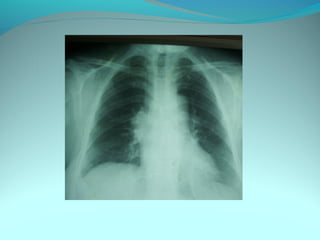

Opacité micronodulaire bilaterale diffuses et uniformement repartis

sur les 2 poumons realisant l’aspect d’une miliaire a petit grain

On note opacité latero trachiale ovalaire de 3cm de grand axe vertical

a limite ext des ADP médiastinale

Une opacité hilaire droite de 15 mm d’epaisseur

DIAGNOSTIC:

Miliaire tuberculeuse avec ADP mediastinal

Lymphome avec miliaire

Sarcoidose type2